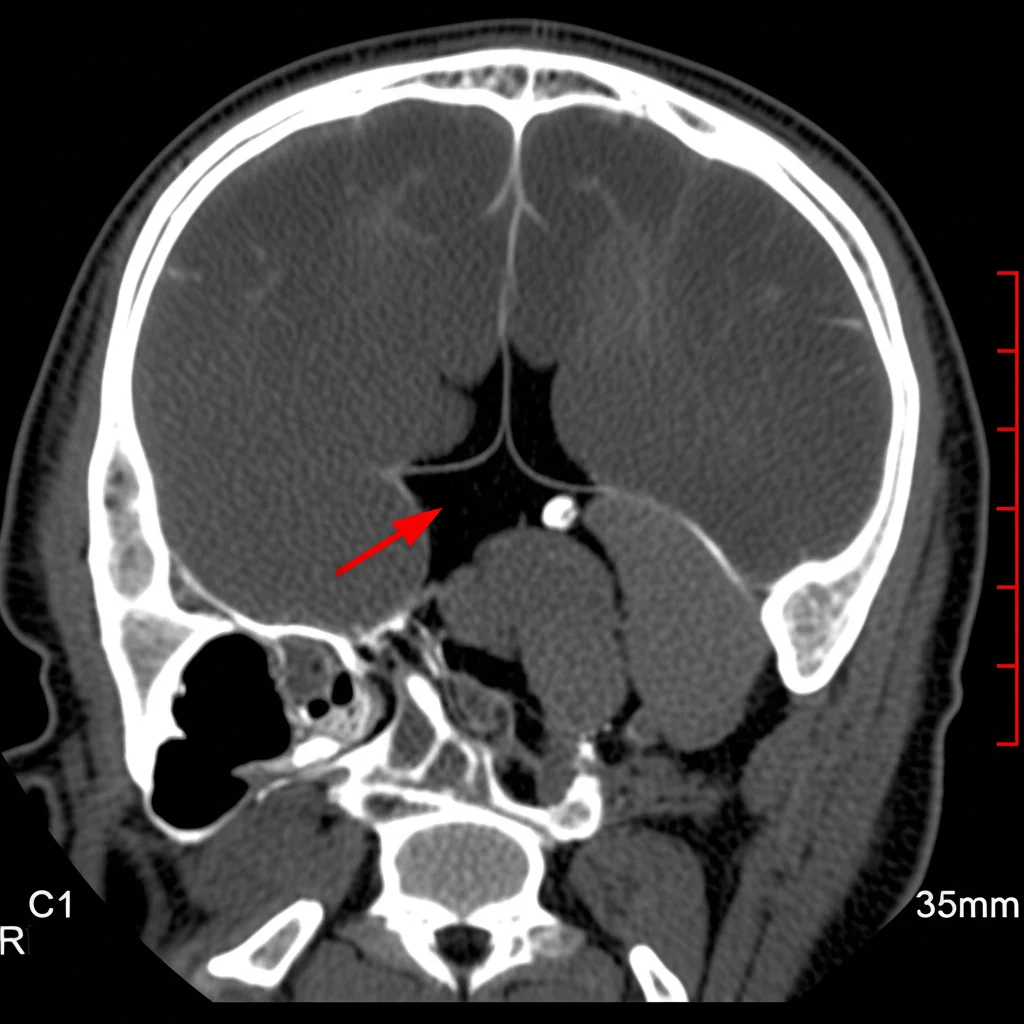

Quando c’è un’emorragia subaracnoidea, la prima cosa che noi medici facciamo è cercare la causa. Spesso si tratta di un aneurisma cerebrale rotto. Eseguiamo quindi un’angio-TC (CTA), un esame che visualizza i vasi sanguigni. Ed ecco la prima sorpresa: l’esame individua un minuscolo punto di contrasto sulla superficie anteriore sinistra del midollo spinale, all’altezza della prima vertebra cervicale (C1). Il sospetto cade su una piccola anomalia vascolare, come un aneurisma o uno pseudoaneurisma. Curiosamente, le arterie principali della zona, come l’arteria vertebrale (VA) e l’arteria cerebellare postero-inferiore (PICA), appaiono del tutto normali, senza stenosi, occlusioni o altre anomalie evidenti.

Passano circa due settimane. Ripetiamo l’angiografia. Ed eccola lì: la struttura simile a un microaneurisma, proprio dove l’avevamo vista inizialmente con la CTA, è di nuovo visibile! Utilizzando una tecnica avanzata chiamata Cone Beam CT, riusciamo a identificare i vasi “madre” di questa piccola sacca: si tratta delle arterie radicolomidollare e radicolopiale, rami appunto della vasa corona. La diagnosi preoperatoria diventa quindi: aneurisma della vasa corona.